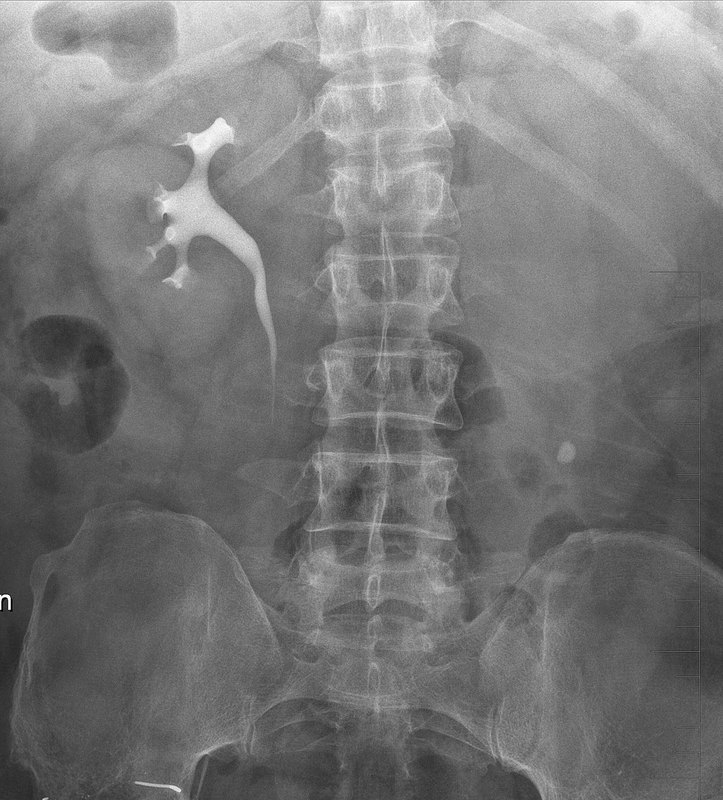

膀胱癌术后输尿管皮肤造口患者,既往一直在外地更换支架管,近期尿液混浊 黏稠度增大,反复发热伴间断寒战,体温最高40度,于外地更换支架管无效,更换后管路迅速堵塞。来我院后完善CT检查提示左侧肾积水,PCT12ng/ml,结合临床表现考虑肾积脓可能性大。给予更换10F支架管,并在控制压力的情况下冲洗肾盂,冲出脓液约100ml,后患者尿液逐步恢复清亮,PCT恢复正常。建议皮肤造口患者尿液混浊尽早处理,积脓后风险极大,也增加了治疗难度。